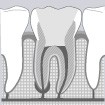

L’endodontie consiste à retirer le ou les nerfs d’une dent. Vos racines seront ensuite rigoureusement nettoyées et désinfectées. La racine sera obturée afin de la rendre étanche. La dent est donc dévitalisée.

1. Tout d’abord le chirurgien-dentiste élimine ce qui reste des tissus vivants infectés ou potentiellement infectés à l’intérieur de la dent (pulpe dentaire).

2. Ensuite, l’intérieur de la dent est nettoyé : élargissement de la surface interne des canaux pulpaires et injection d’une solution désinfectante.

3. Le système canalaire est mis en forme de manière à laisser pénétrer la solution d’irrigation sur toute la longueur de la racine. Cette solution est ensuite séchée.

4. Dernière étape : réalisation de l’obturation canalaire, à l’aide de connes de gutta percha et d’un ciment oxyde de zinc-eugénol.